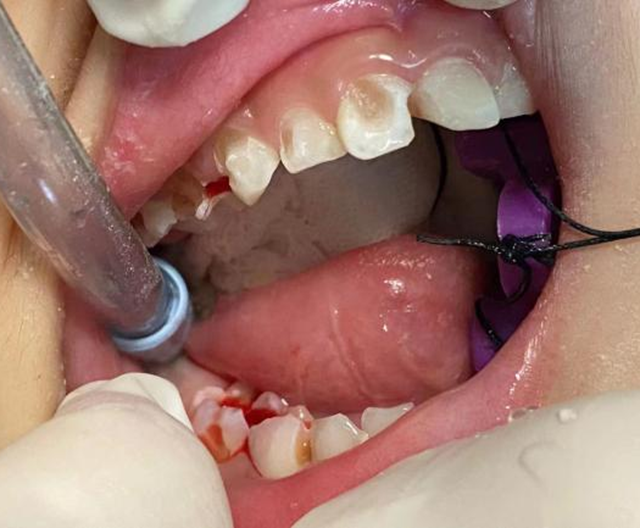

到了手术时间,麻醉科医生为豪豪实施了全身麻醉,黄丹很顺利地为豪豪完成了治疗。手术结束后,豪豪就复苏了,黄丹给家长交代了注意事项后,他们就回家了。

首先患儿坏牙多,就诊次数多,增加了就诊成本;其次许多口腔问题需要局麻伴有疼痛,患儿不配合还容易对口腔治疗产生阴影,例如根管治疗、拔除难度较大的牙、唇舌系带修整术等,这时全麻下舒适化口腔治疗就是最佳的选择。

在全麻下可以安全、高效地一次性完成儿童口腔内所有患牙的治疗,解除患儿的焦虑和疼痛,节省了患儿家长的时间,减少就诊次数,提高了诊疗效率。